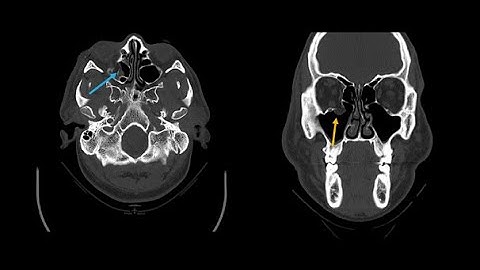

Skull Fractures - 360 View of CT Scans